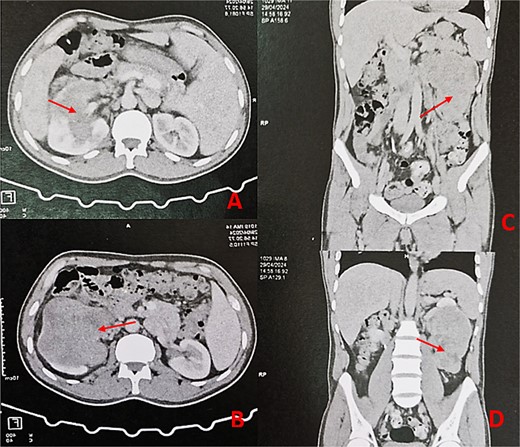

A 44-year-old patient presents to a urologist with gross hematuria and left flank pain that has been ongoing for the last 4 months. An ultrasound was followed by a thoraco-abdominopelvic computed tomography (CT) scan, which revealed a large renal mass centered on the middle and lower third of the left kidney, infiltrating the entire calyceal system up to the left ureter. Additionally, there is perirenal fat infiltration (Fig. 1). The patient underwent a radical nephrectomy, and the specimen was sent to the pathology laboratory for histopathological examination. Gross examination of the radical nephrectomy specimen revealed a polylobulated, firm, white yellow tumor appearing to infiltrate the renal sinus and hilum, reaching the renal capsule without perirenal fat infiltration (Fig. 2). No macroscopic tumor embolus was observed in the renal vein. Lymphadenectomy of the perirenal fat revealed a lymph node measuring 1.1 × 0.8 × 0.5 cm.

Thoraco-abdominopelvic CT scan with axial (A, B) and sagittal (C, D) images demonstrating a large heterogeneous mass (arrows) centered on the middle and lower thirds of the left kidney.